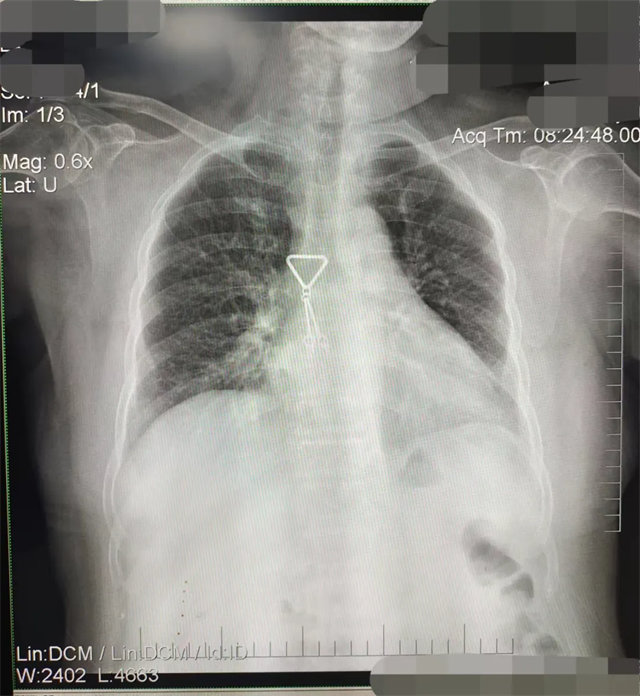

缺陷:兩肩胛骨未拉開肺野之外,吸氣不完全,且存在金屬飾品遮擋。

解決:去除金屬飾品及內衣后重新按標準體位攝片即可。